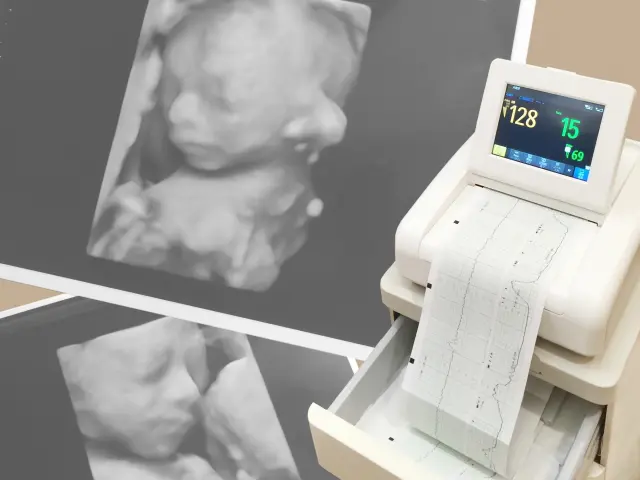

胎児ドックは、妊娠中に胎児の健康状態や異常のリスクを評価するために行われる検査です。この検査は、胎児の形態的な異常を早期に発見し、染色体異常のリスクを推定することで、妊婦とその家族に安心をもたらします。主に超音波検査を使用して、医師が胎児の成長状況や健康状態を細かく確認します。

この時期は、染色体異常のリスク評価や初期の形態異常の発見が主な目的です。NT測定(首の後ろの透明層の厚さの測定)が行われます。 - 妊娠18〜22週(中期胎児ドック)

胎児の形態異常、特に心臓や四肢、内臓の異常を重点的に評価します。この時期が最も異常を見つけやすいとされています。 - 妊娠28〜32週(後期胎児ドック)